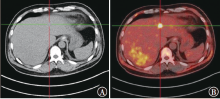

Yi LL, Zhang JX, Zhou SG, et al. CT and MRI studies of hepatic angiosarcoma[J]. Clin Radiol, 2019, 74(5): 406. e1-406.e8. DOI: 10.1016/j.crad.2018.12.013.

doi: 10.1016/j.crad.2018.12.013